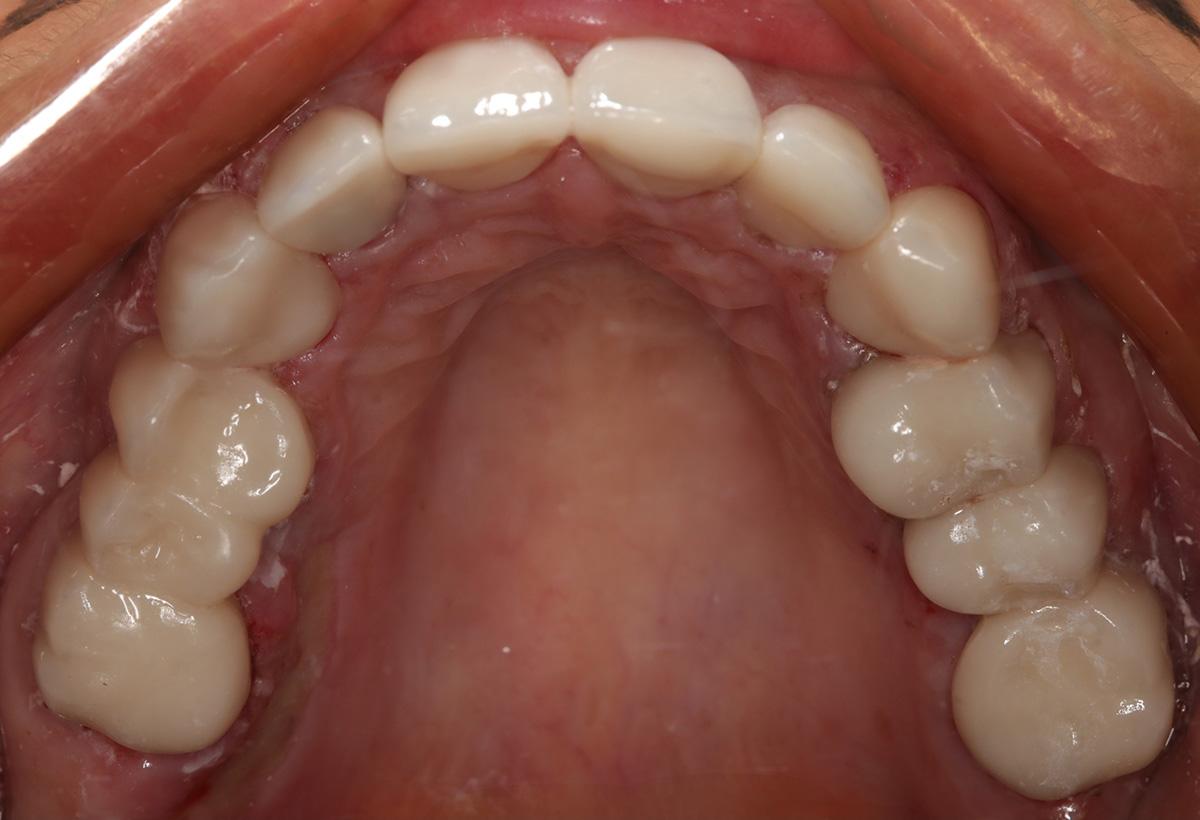

Pacjentka została objęta w naszej Klinice kompleksowym leczeniem implanto-protetycznym.

Podczas gdy w dolnym łuku dr Michał Mokijewski przeprowadzał zabiegi regeneracyjne i implantacje, zajęłyśmy się leczeniem łuku górnego.

Zgodnie z zasadą, że prace protetyczne powinny być oparte na zdrowych i solidnych fundamentach, zaczęłyśmy od podstaw – wymiana nieszczelnych wypełnień, powtórne leczenia kanałowe.

Praca została zwieńczona odbudową zębów koronami cyrkonowymi. Brakujący ząb, którego nie można było uzupełnić implantem z powodu za małej ilości miejsca, odtworzono za pomocą cyrkonowego mostu.

Zgodnie z życzeniem Pacjentki poprawiony został kolor i kształt zębów. Kamuflaż protetyczny umożliwił także skorygowanie asymetrii.

Dzięki profesjonalizmowi naszych lekarzy, Pacjentka ma teraz zdrowy, piękny uśmiech!